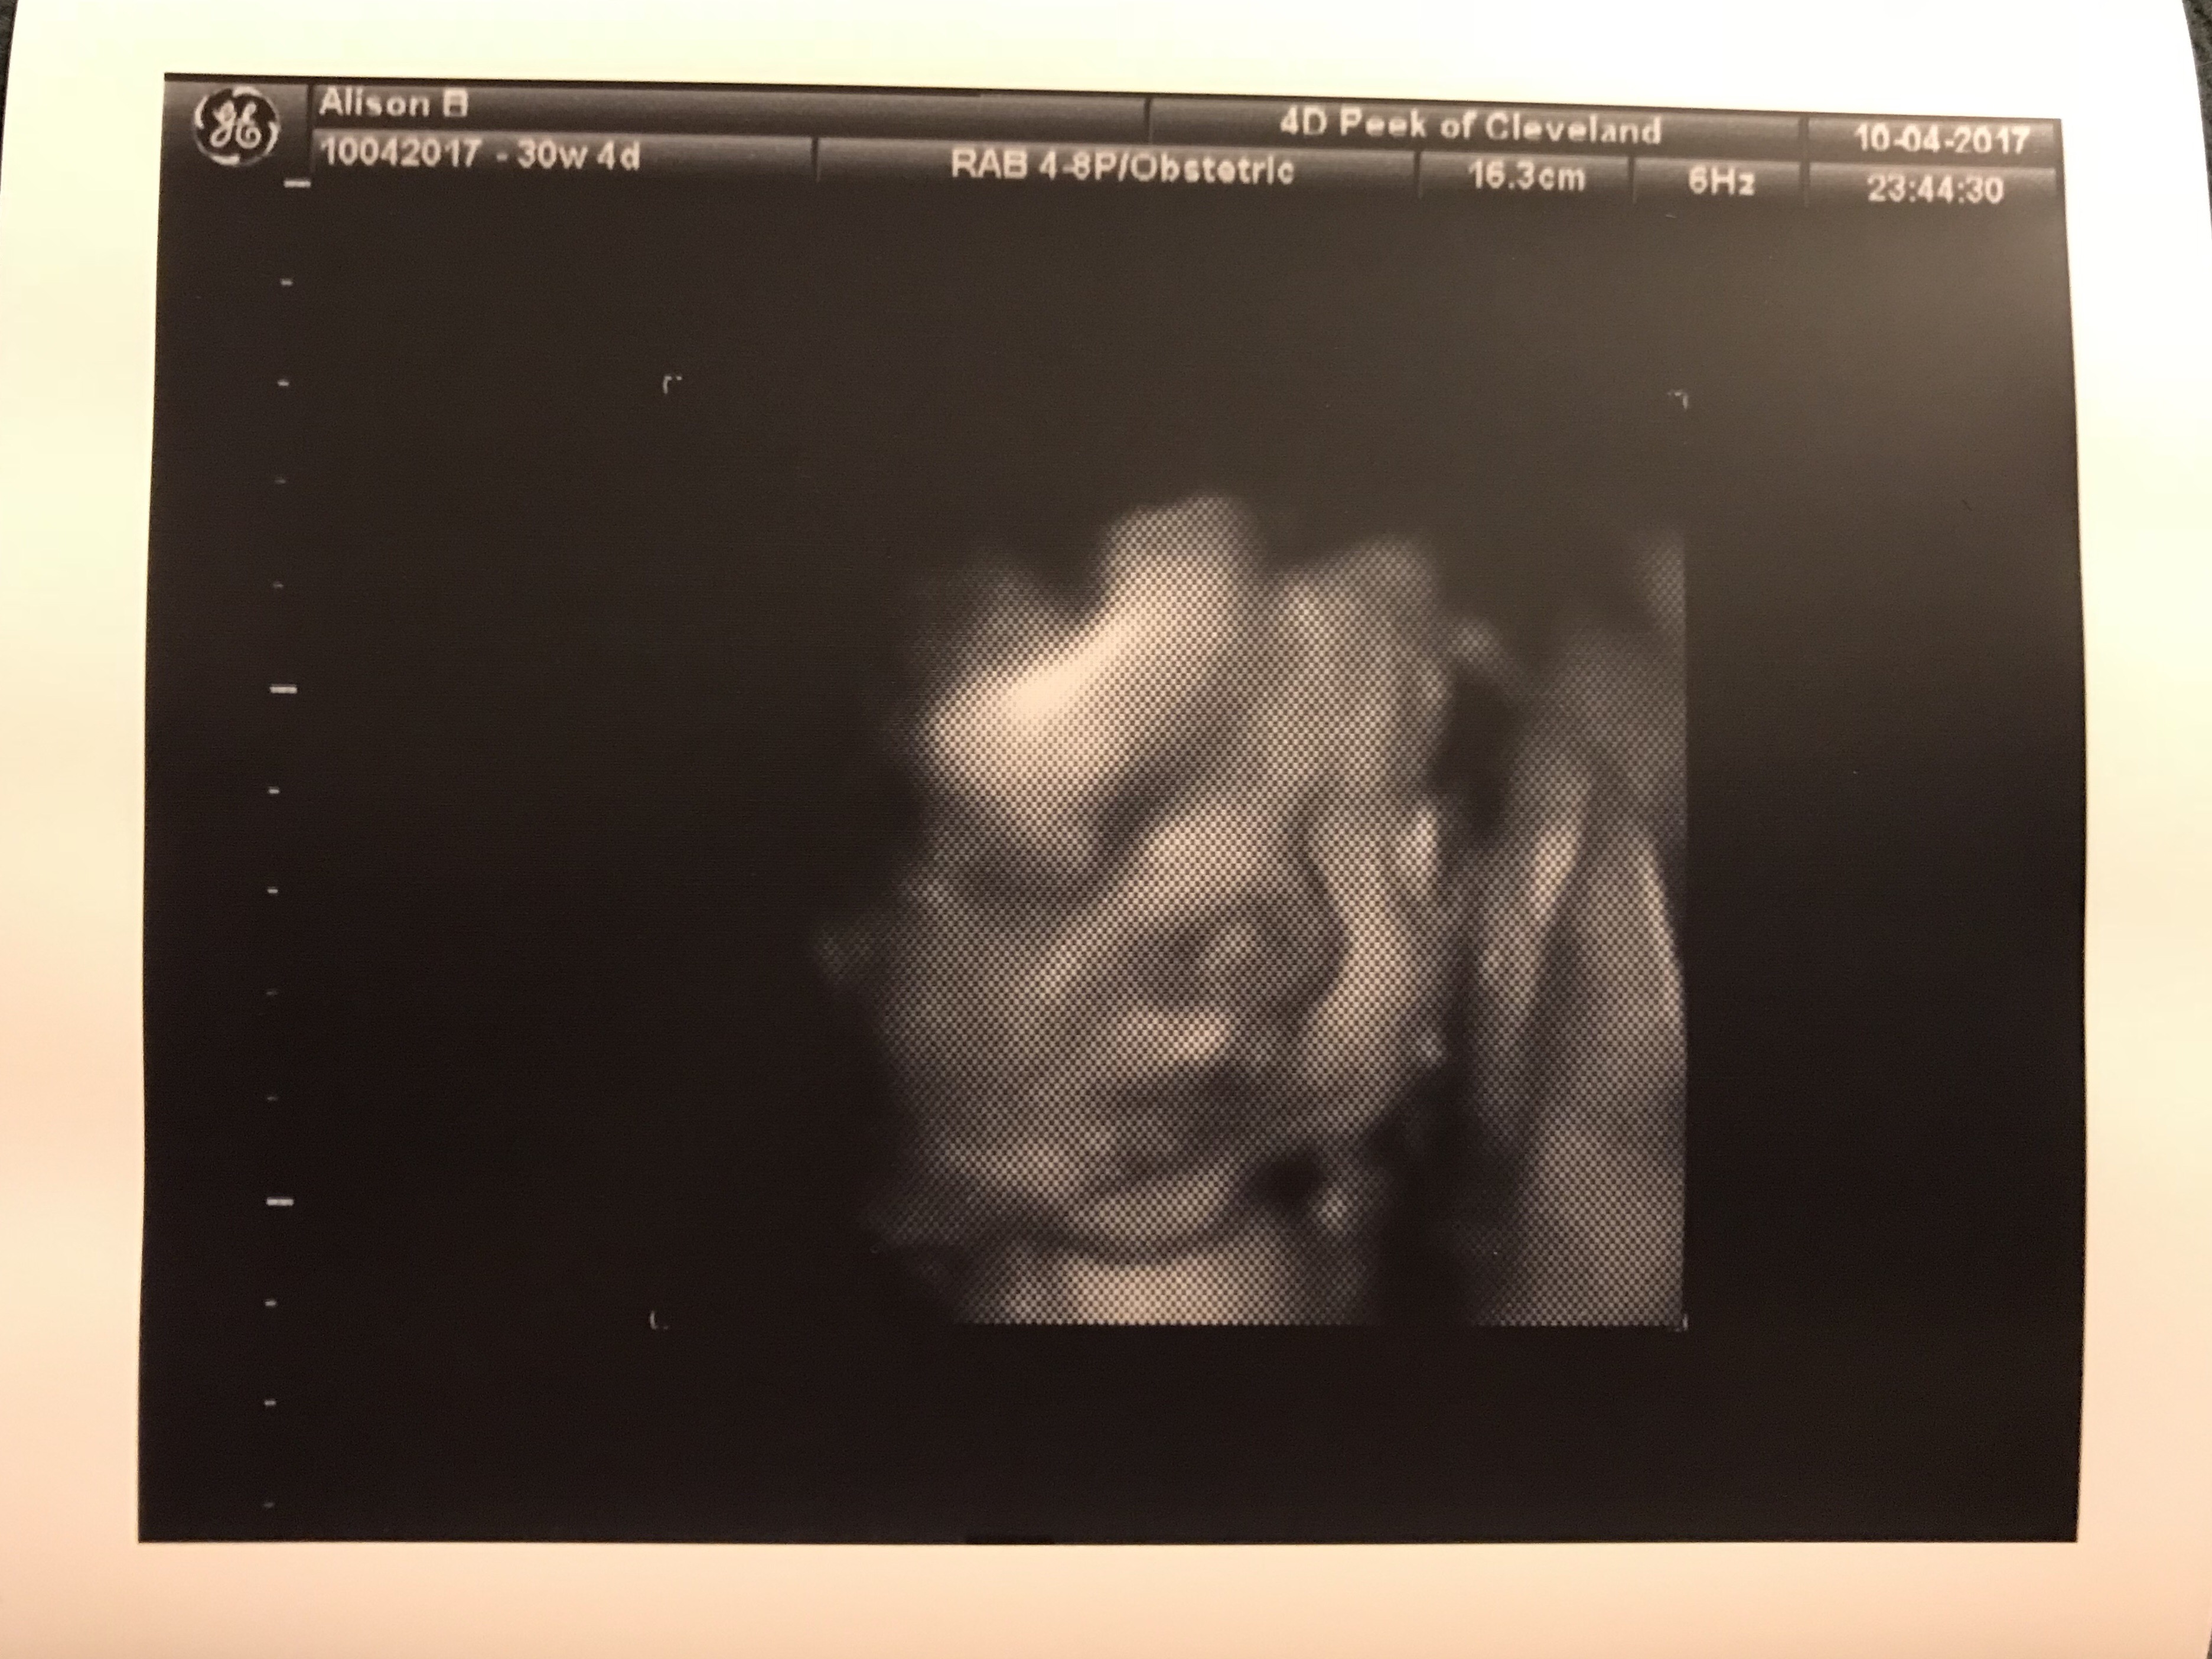

Baby Eugene’s Grammy Ronda and Grandpa Hank headed to Florida this week and before they left, we wanted to get together for a 4D ultrasound. We hoped to do that with my dad as well so he could see Eug for himself but he got so sick so fast that we just didn’t get the chance. When we called to make the appointment they said they’ve had as many as eighteen people in an ultrasound at once so we figured we’d invite all of our peeps! Emily had another engagement so we knew she wasn’t coming and we weren’t sure if Grandpa Hank and PapPap would want to come so imagine our surprise when we walked into the clinic and found six people waiting for us! Emily surprised me and the guys came along and we couldn’t have been happier to share in our first real glimpse at our baby’s features! Here’s some of the images:

We decided that he definitely has Shane’s mouth, probably my nose but maybe it’s Emily’s/Dad’s, and – yes Kiplings – the famous Kipling cheeks! He also enjoys his feet – they hung out in front of his face for a good chunk of the session but regardless, it was a wonderful evening of sneaking a peek at this beautiful baby (and yes we confirmed it!) boy!